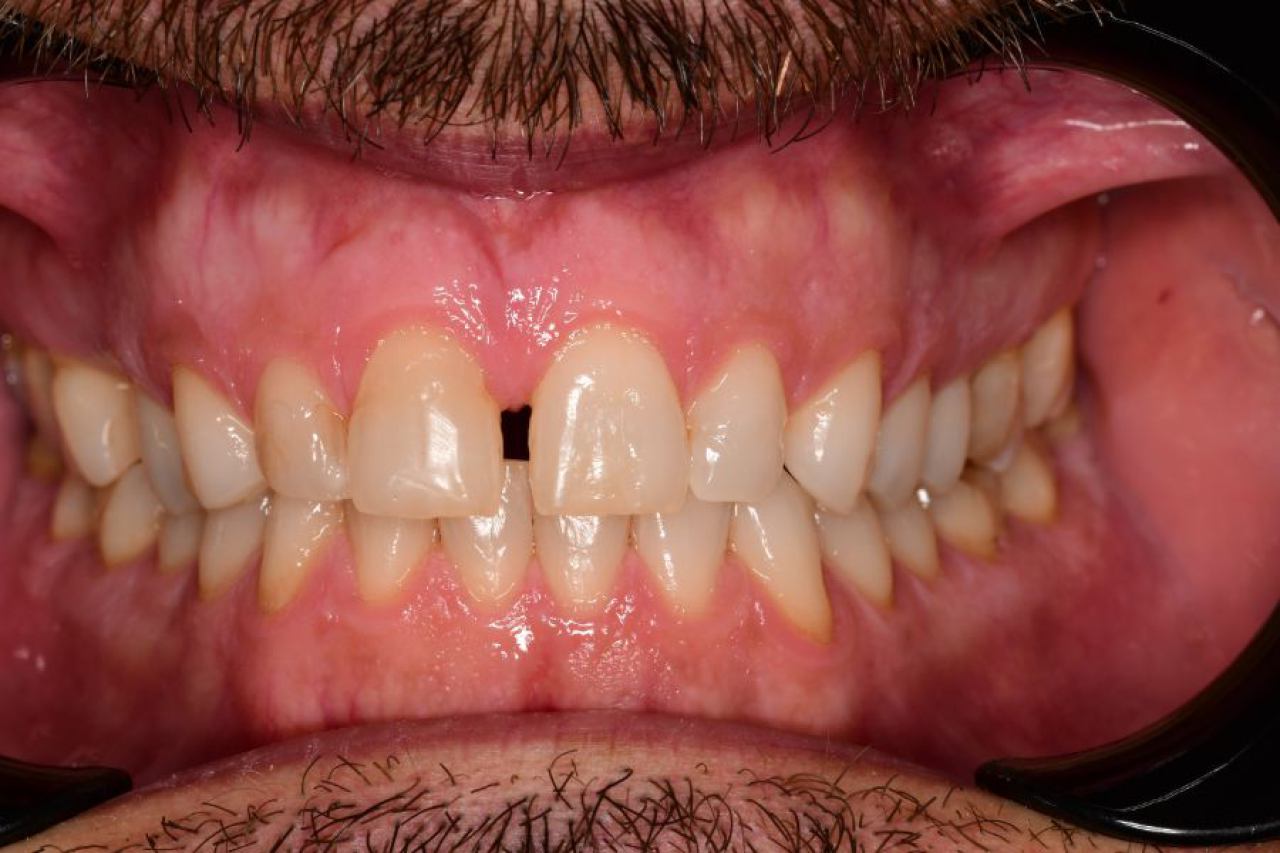

Protetika - mostovi i krunice

Dentalna protetika uključuje fiksne i mobilne radove kojima se nadoknađuje djelomična ili potpuna bezubost. Njihov cilj je povratiti funkciju žvačnog sustava i u konačnici, vrhunsku estetiku.

Marković Dental Clinic u svojoj ponudi ima metalkeramičke radove, potpunokeramičke radove, te u narodu zvane „bezmetalne", odnosno zirkonske radove.